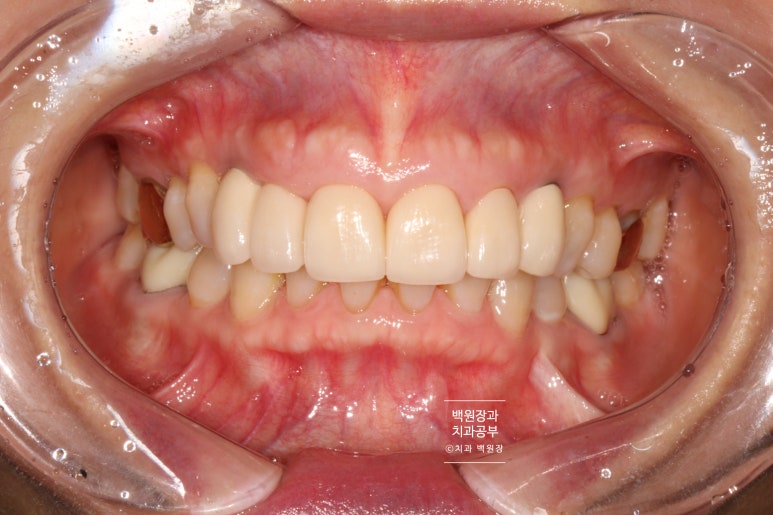

충치가 심했던 송곳니를 뽑고 약 3.5개월 후 드디어 완성의 날..

4개의 앞니를 지르코니아 크라운으로 제작하였고, 2개의 송곳니를 임플란트로 제작해드렸습니다.

상당히 자연스러운 색상과 외형을 가진 보철물로 제작이 잘 되었네요!

여성분이라 잇몸의 두께가 얇아 임플란트의 경우 내부의 맞춤형 지대주 (custom abutment)가 약~간 비춰보이는 경향은 있으나, 사실 본인이 아니고서야 이게 자연치인지 크라운인지 임플란트인지 분간조차 어려울 거에요.

아주 조금의 아쉬움이라 할 수도 있겠으나, 한편으론 더 잘닦아내실 수 있는 형태이기도 합니다.